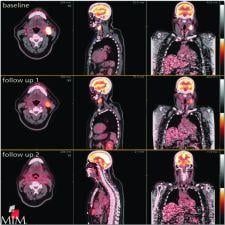

MIMvista's MIMfusion serial exam aims to eliminate labor-intensive, multistep processes such as fusion, linking and layouts. With MIMvista’s customizable workflows, any number of exams can reportedly be linked or fused automatically for easy comparison. For example, tumors may be tracked and correlated over multiple time points. Tumors may be defined with PET Edge on serial PET exams with provide quantitative analysis All ROI statistics may be exported to a spreadsheet for reportedly streamlined reporting, according to the company.